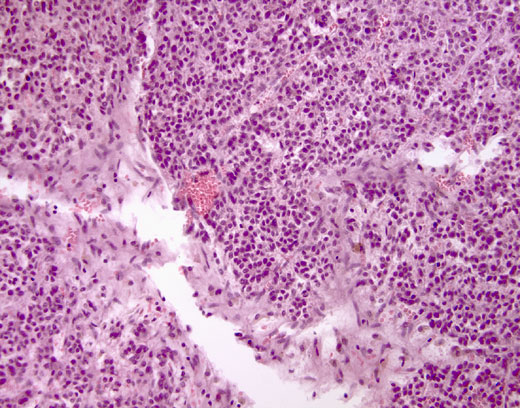

Cross-section #17 - 20X

click on the slide photo to see 40X magnification